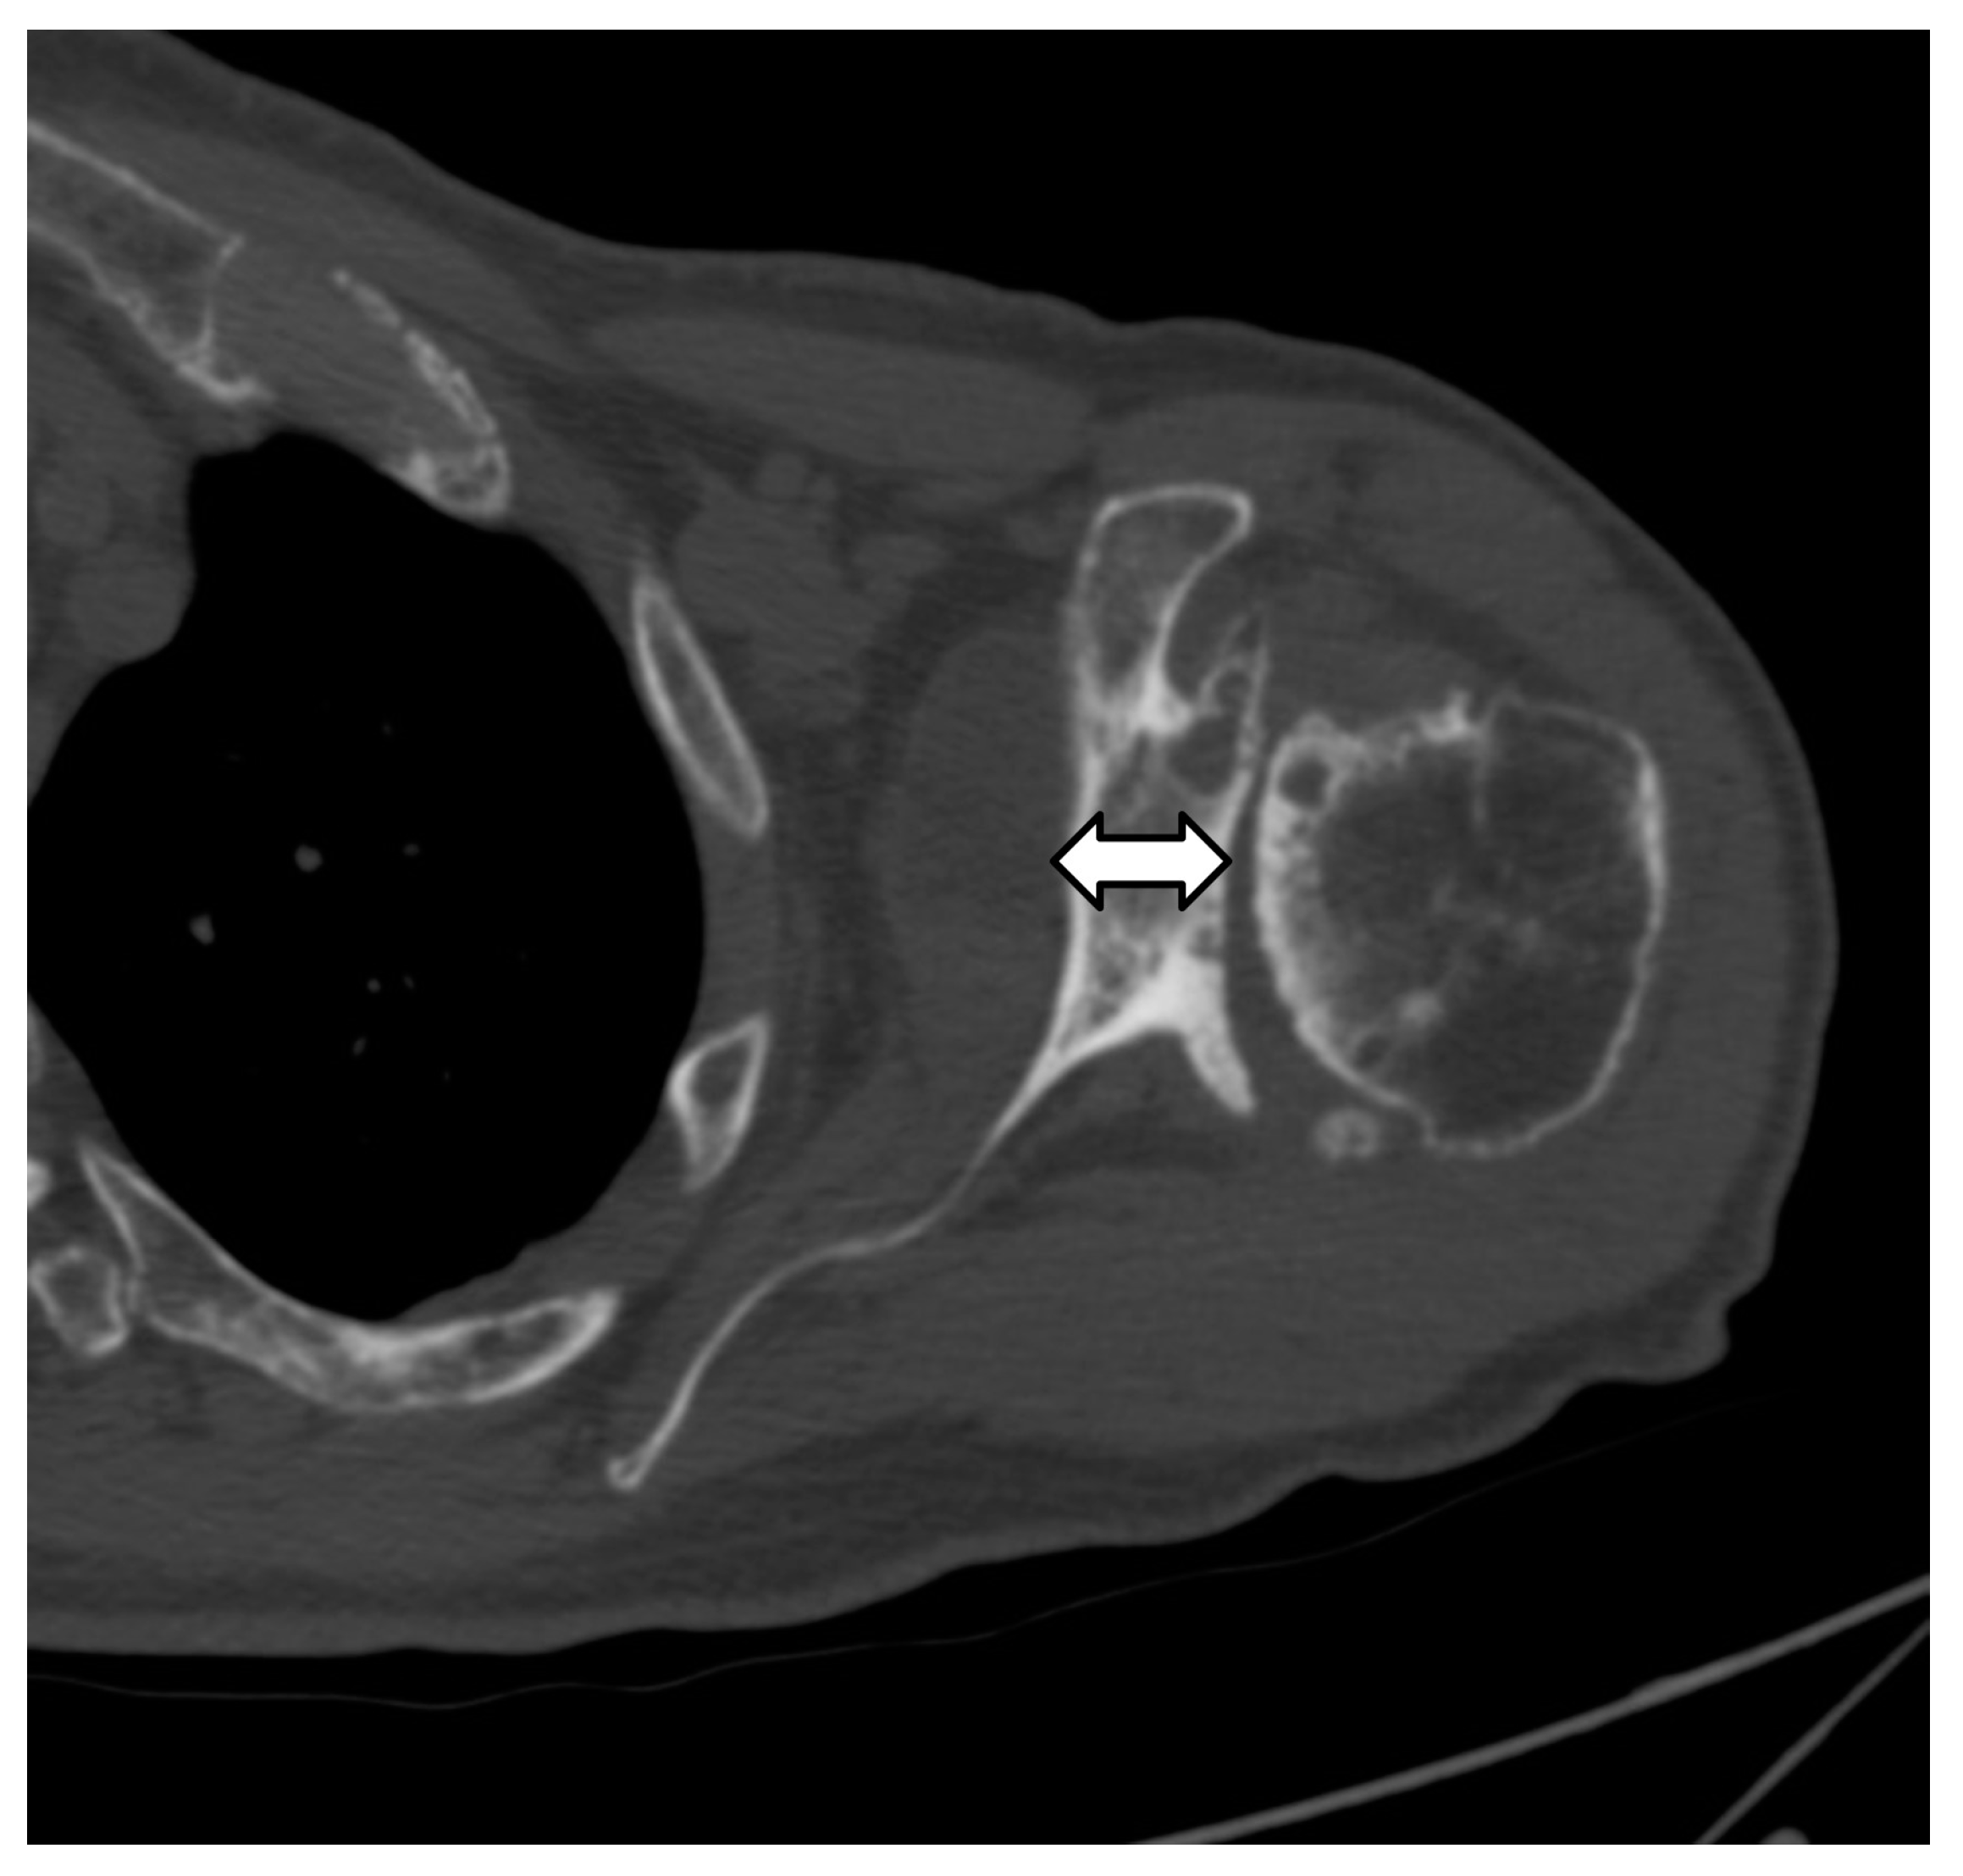

3. Preoperative Imaging

| Type | Description |

| B1 | No glenoid erosion; posteriorly subluxed humeral head with posterior joint space narrowing and osteophytes. |

| B2 | Biconcave glenoid due to posterior erosion and retroversion, with posteriorly subluxed humeral head. |

| B3 | Monoconcave glenoid with significant posterior glenoid wear with retroversion of at least 15 degrees or subluxation of 70% or both. |